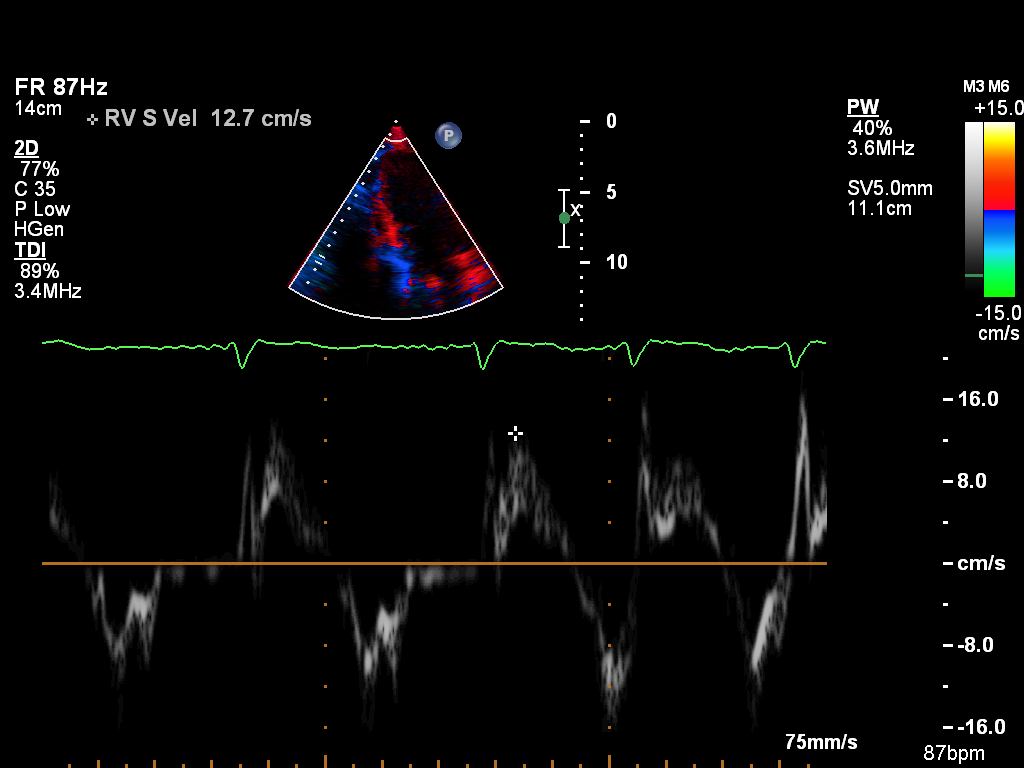

doppler-tissue-rv doppler-tissue-rv Tissue Doppler of the RV free wall

doppler-tissue-septal doppler-tissue-septal Tissue Doppler of the LV septal wall